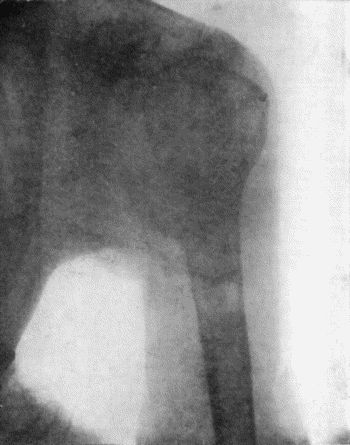

136.Osteomyelitis Fibrosa affecting Femora 476

137.Radiogram of Upper End of Femur in Osteomyelitis Fibrosa 478